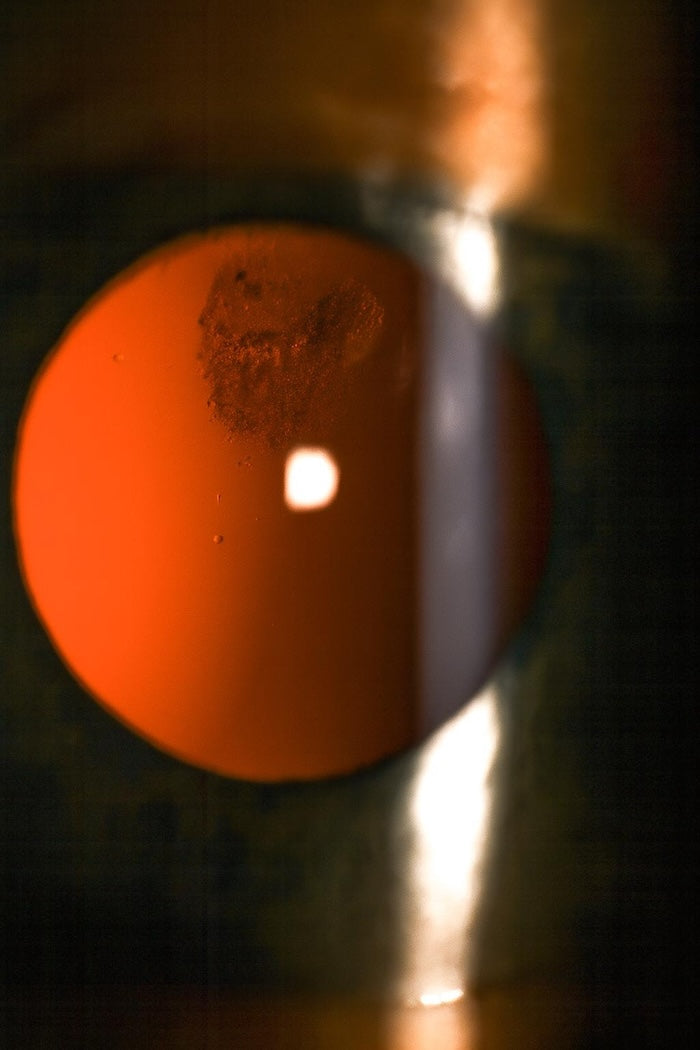

Familiárna exudatívna vitreoretinopatia

Zriedkavé dedičné vitreoretinálne ochorenie Criswick Schepens (FEVR - Familiárna exudatívna vitreoretinopatia).